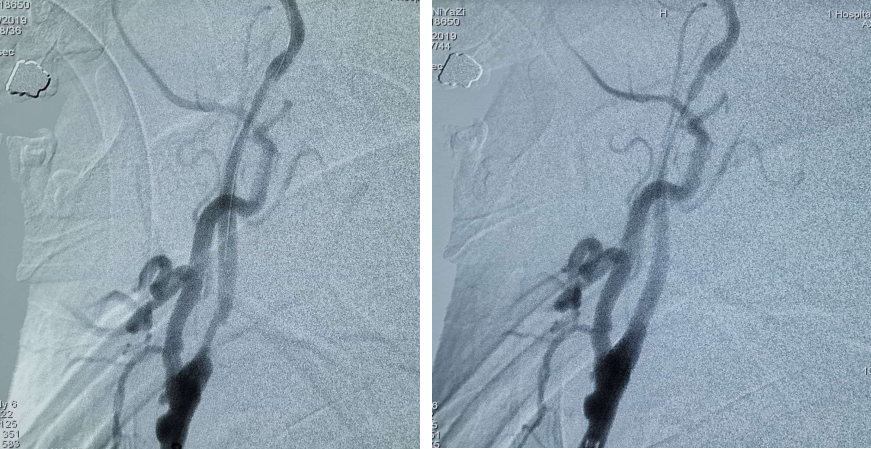

术中造影及手术过程

全脑血管造影术提示:左侧颈内动脉起始部闭塞,左侧颈内颅内段未见显影;在颈内动脉起始部采用Rebar-18微导管采用SWIM(支架取栓+抽吸)技术。

支架于血栓充分贴合后取栓系统回收,复查造影示:左侧大脑中动脉远端未见显影;Silverspeed14微导丝携带Rebar-18微导管到达左侧颈内动脉M2段,采用SWIM技术后复查造影血流通畅。

PT导丝携带颈动脉支架通过左侧颈内动脉狭窄处,释放支架后复查造影支架贴壁良好狭窄率不足10%。

术后复查左侧颈内动脉颅内段血供良好